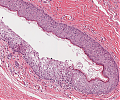

Reifes_zystisches_Teratom1_A94.png

Reifes zystisches Teratom ausgekleidet von verhorntem Plattenepithel.

Reifes_zystisches_Teratom_A94.png

Reifes zystisches Teratom mit Ausbildung von Talgdrüsen.